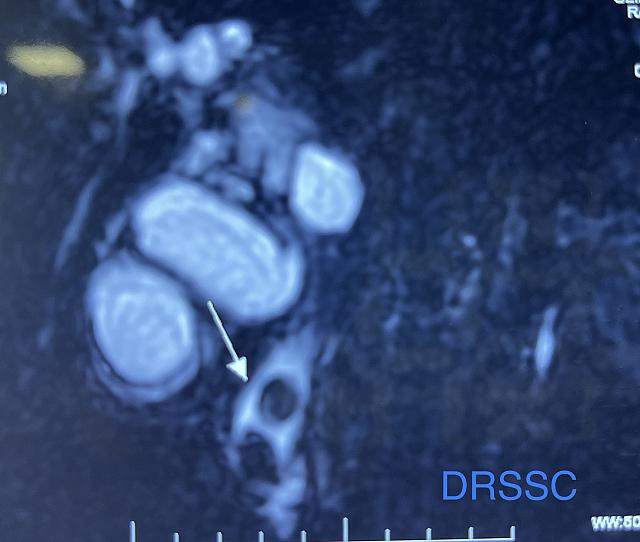

LAPAROSCOPIC SUBTOTAL CHOLECYSTECTOMY

- - SMALL PART OF GALL BLADDER LEFT CLOSE TO CBD

- - DONE TO AVOID CBD INJURY

- - USEFUL IN PATIENTS WITH FROZEN CALOT’S TRIANGLE